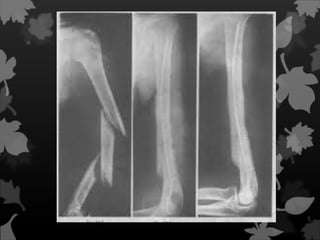

Esse tipo de fratura ocorre de

fraturadas. As principais formas de

fraturas ósseas completas são:

Fratura longitudinal

Quando há

ruptura

ao longo do osso.

Fratura oblíqua

São

decorrentes

de lesões que

ocorrem com

uma torção.

Fratura Espiral

É quando o

traço de

fratura

encontra-se ao

redor e

através do

osso.